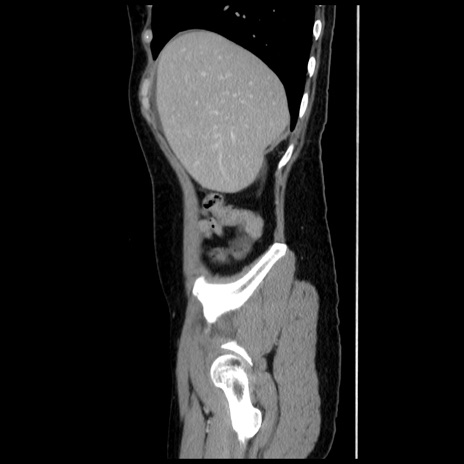

冠状断像

【症例】 50歳代女性

【主訴】 腹痛

【現病歴】前日生レバーを食べた。今朝に排便あり。 昼前に突然発症の腹痛を生じ、当院救急外来を受診した。

【既往歴】 子宮筋腫にてで子宮全摘後

【身体所見】 意識清明、腹部:平坦、軟、下腹部やや左を中心に圧痛・反跳痛あり、筋性防御あり

【データ】WBC 7800、CRP 0.07